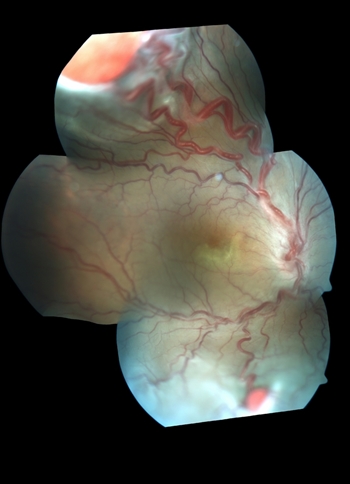

Retina Image Bank: Image of the Day

Condition: Von Hippel-Lindau disease

Photographer: Gabriela Lopezcarasa Hdz. Hospital Angeles Lomas

Imaging device: Fundus cameras, FF4

Description: 29-year-old woman with decrease in visual acuity secondary to serous retinal detachment in Von Hippel-Lindau disease